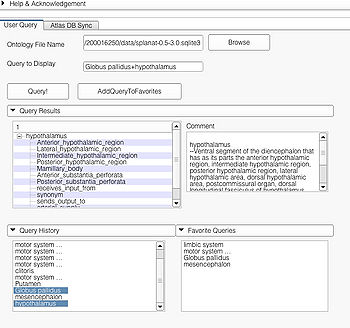

User Query Page

This page is useful for creating visualizations based on user typed queries. The user inputs consist of the Ontology File Name and Query To Display. The button Query fires a query and causes the module to start processing the user query for visualization. The button AddQueryToFavorites adds the last typed user query to the list of favorite queries. The favorite query list is shown in the bottom panel Favorite Queries. Additionally, the interface also shows a history of typed queries in the panel Query History.

The Query Results panel shows the result of a query, consisting of all the associated predicates and parts for the query. The Figure User Page GUI shows the result of a simple query "limbic system".Additionally, the interface also shows a Comment that contains any relevant textual information about the query obtained from the ontology. The user can refine a search by selecting from the query result. Optionally, the user can also select by clicking on any selection from the Query History or Favorite Queries panel to redo search and visualization. The interface supports the multiple selections to form complex queries. The visualization resulting by searching with the query "Limbic system" is shown below.

- Simple Queries e.g. "putamen", "limbic system"

Simple query is a self-contained individual string that is matched in entirely with the ontology. An example of a simple query is "limbic system". The result of this query is shown above.

Complex Queries

A complex query contains two or more simple or specialized queries. A complex query is typically specified by using a "+". Note that the "+" does not signify an ANDing of the search terms. Instead each string separated by the "+" is searched as an individual query in the ontology. The result of using a complex query is shown below. The Application interface shows the results for all the terms that are matched in the ontology (i.e. the motor system and straight gyrus.) Unmatched terms such as the user added models (e.g. mass) are only displayed. The figure shows an example of a complex query comprised of simple queries.

Specialized Queries

A specialized query helps to search for a query with additional constraints typically using an ANDing operation. Specialized query is specified using a ";" between the search terms. In terms of search in the ontology, the ";" will either result in a search involving the first term as the Subject or Object and the second term as the Predicate(e.g. "straight gyrus;synonym"). In the case where the second term is not a predicate but a part of the preceding term, e.g. "limbic system;Fornix", the visualizer logic automatically detects that the succeeding term is an individual search term and produces the visualization using the succeeding term as the search string resulting in the visualization of query "Fornix".

Specialized queries can be combined with other simple or specialized queries to form complex queries (e.g. "motor system + straight gyrus;synonym"). An example of a complex query using specialized and simple query terms is shown below.